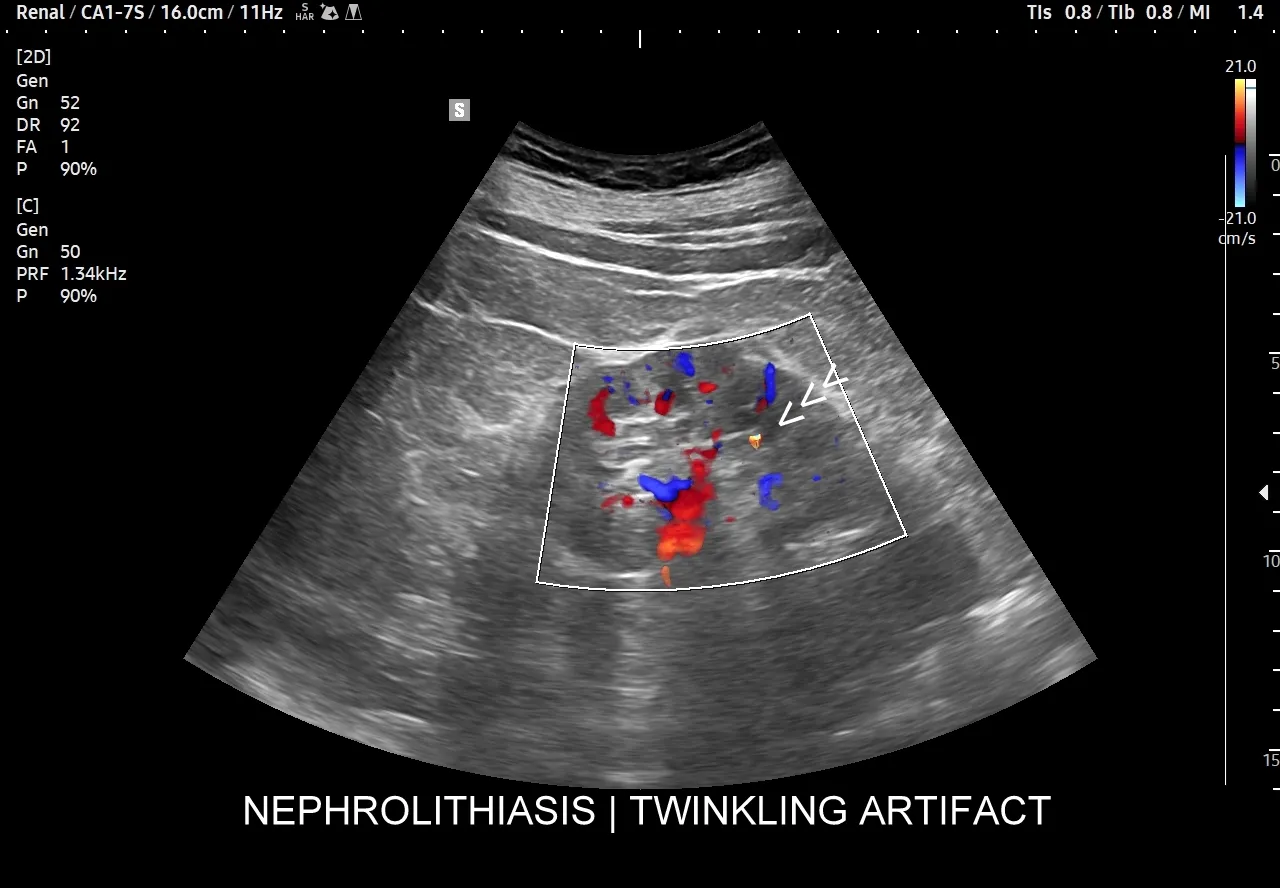

Aby "zajrzeć do środka" i dokładnie ocenić stan nerek, niezbędne są badania obrazowe. Najczęściej zaczynamy od USG układu moczowego. Jest to badanie nieinwazyjne, łatwo dostępne i pozwala szybko ocenić wielkość nerek, obecność kamieni, torbieli, wodonercza czy większych guzów. Jest to doskonałe narzędzie przesiewowe. Jeśli USG nie daje jednoznacznych odpowiedzi lub podejrzewam bardziej złożone problemy, sięgam po bardziej zaawansowane metody. Tomografia komputerowa (TK) jest niezwykle precyzyjna w wykrywaniu kamieni nerkowych, nawet tych bardzo małych, a także w ocenie guzów i zmian strukturalnych. W niektórych przypadkach, zwłaszcza gdy potrzebujemy szczegółowej oceny tkanek miękkich, naczyń krwionośnych lub gdy pacjent nie może być narażony na promieniowanie rentgenowskie (np. kobiety w ciąży), zlecany jest rezonans magnetyczny (MRI). Każde z tych badań ma swoje specyficzne zastosowanie i pomaga mi uzyskać pełny obraz sytuacji, co jest kluczowe dla postawienia trafnej diagnozy i wdrożenia skutecznego leczenia.